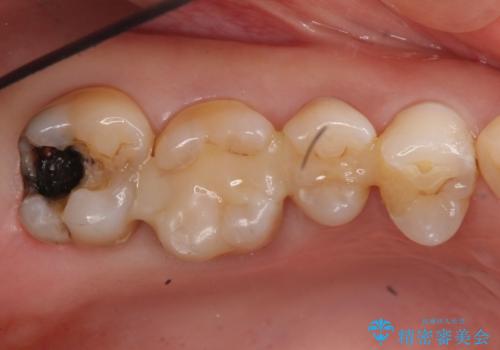

- 虫歯治療を希望して来院。

保険適用の銀色のつめもののやり替えを行いました。

自由診療のインレーの歯型には、シリコンを使用しています。また、処置時には8倍の拡大鏡を用いて、精密に治療しております。